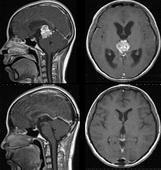

髓內腫瘤癥狀

• 髓內腫瘤

628健康網為您分享有關髓內腫瘤的癥狀,髓內腫瘤的治療方法,髓內腫瘤的預防知識,髓內腫瘤的癥狀圖片,髓內腫瘤吃什么藥,髓...